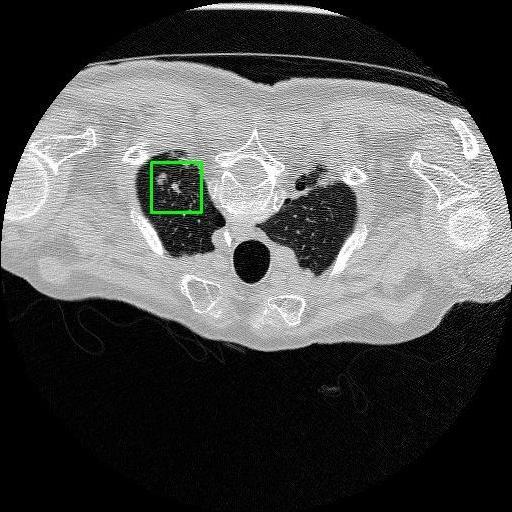

We developed an AI-based system using deep learning models for analyzing lung CT scans to detect and classify pulmonary nodules. We chose the YOLOv11 architecture for its enhanced object detection capability and adapted it specifically for medical imaging, incorporating pixel-level precision and severity classification.

Classification into three severity levels with colored bounding boxes.

Successfully built and deployed an AI model (YOLOv11) capable of detecting lung nodules in CT scans with high accuracy and real-time performance.

Designed a severity classification system that categorizes nodules into null, moderate, and severe using colored bounding boxes, assisting in rapid clinical decision-making.